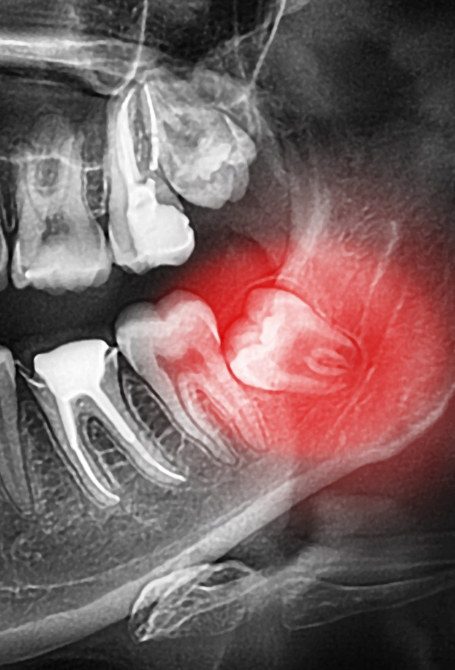

We offer customized care for teeth and soft tissues affected by various degrees of disease. Whether it's more or less deep-seated decay, gingivitis, periodontitis or abscesses, we know how to stop the pathology and treat its consequences, if need be.